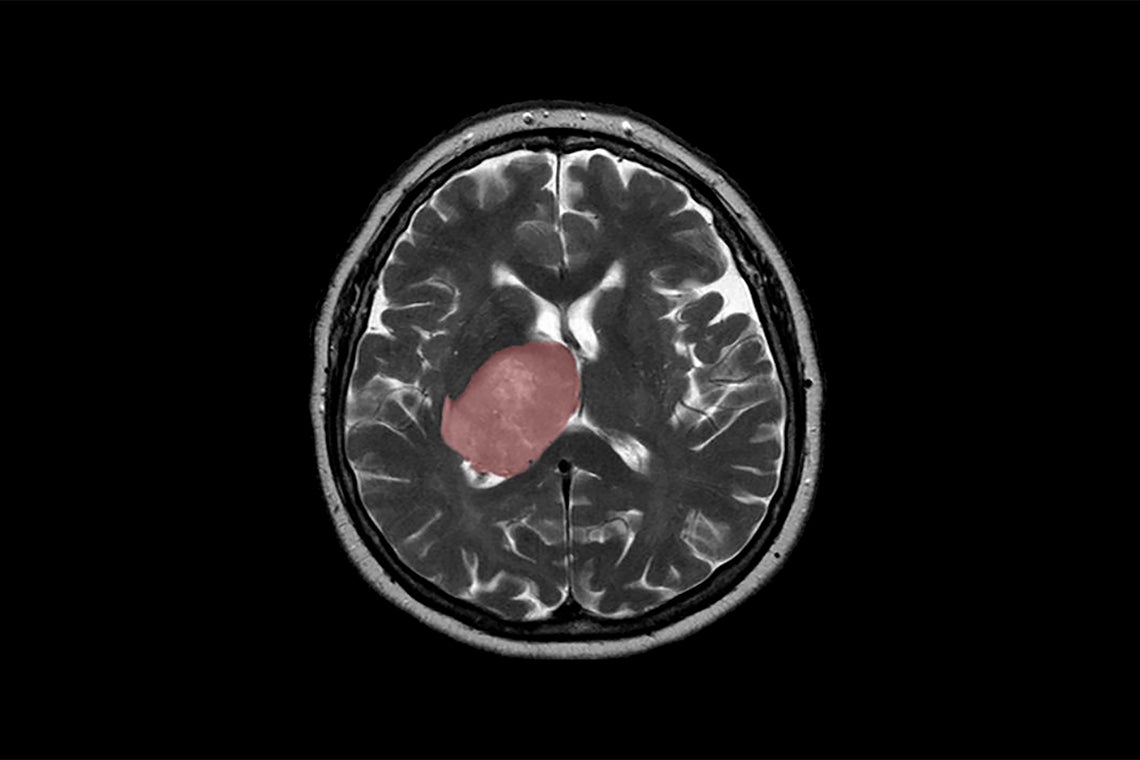

(photo by Hellerhoff)

Glioblastoma is the most common and aggressive form of brain cancer owing to tumour heterogeneity at the molecular level and its ability to evolve into new forms that resist therapy. Standard treatment involves surgery, radiation and chemotherapy but most patients relapse within seven to nine months, while median survival between diagnosis and death has not extended beyond 16-20 months over the past decade.